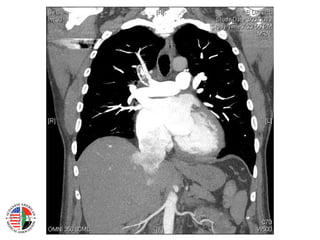

CT Chest – PE Protocol

CT Chest –PE Protocol